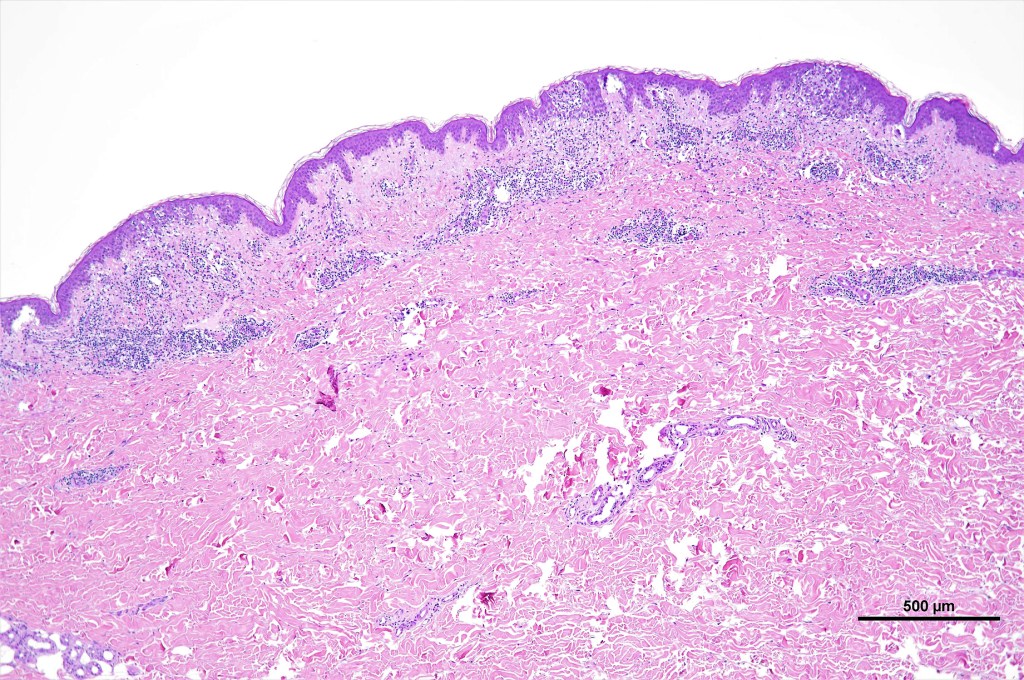

•Type A: 75-80%, wedge shaped infiltrate with base uppermost, large, anaplastic cells with abundant cytoplasm and vesicular nuclei containing prominent nucleoli, can resemble Reed-Sternberg cells, conspicuous mitoses & background infiltrate of lymphocytes, plasma cells, histiocytes, neutrophils & eosinophils